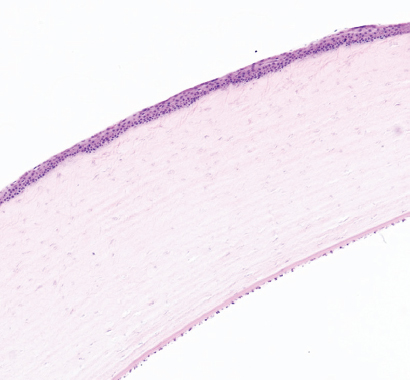

Режим 5. На данном сроке эксперимента строма роговицы в месте воздействия незначительно уплотнена (примерно на 35–40 %). Место воздействия полностью покрыто многослойным эпителием, однако выделяются места с истончённым эпителием и места с резко утолщённым эпителием. Строма роговицы под эпителием представлена плотно лежащими коллагеновыми волокнами. Десцеметова мембрана и энодотелий без изменений (рис. 8).

Рис. 8. Фрагмент роговицы после воздействия в подгруппе 1б. Кросслинкинг + фульгурация, режим 5. Окраска гематоксилином и эозином. Увеличение ×40

Fig. 8. Fragment of the cornea after exposure in subgroup 1b. Cross-linking + Fulguration, mode 5. Stained with hematoxylin and eosin. Magnification ×40